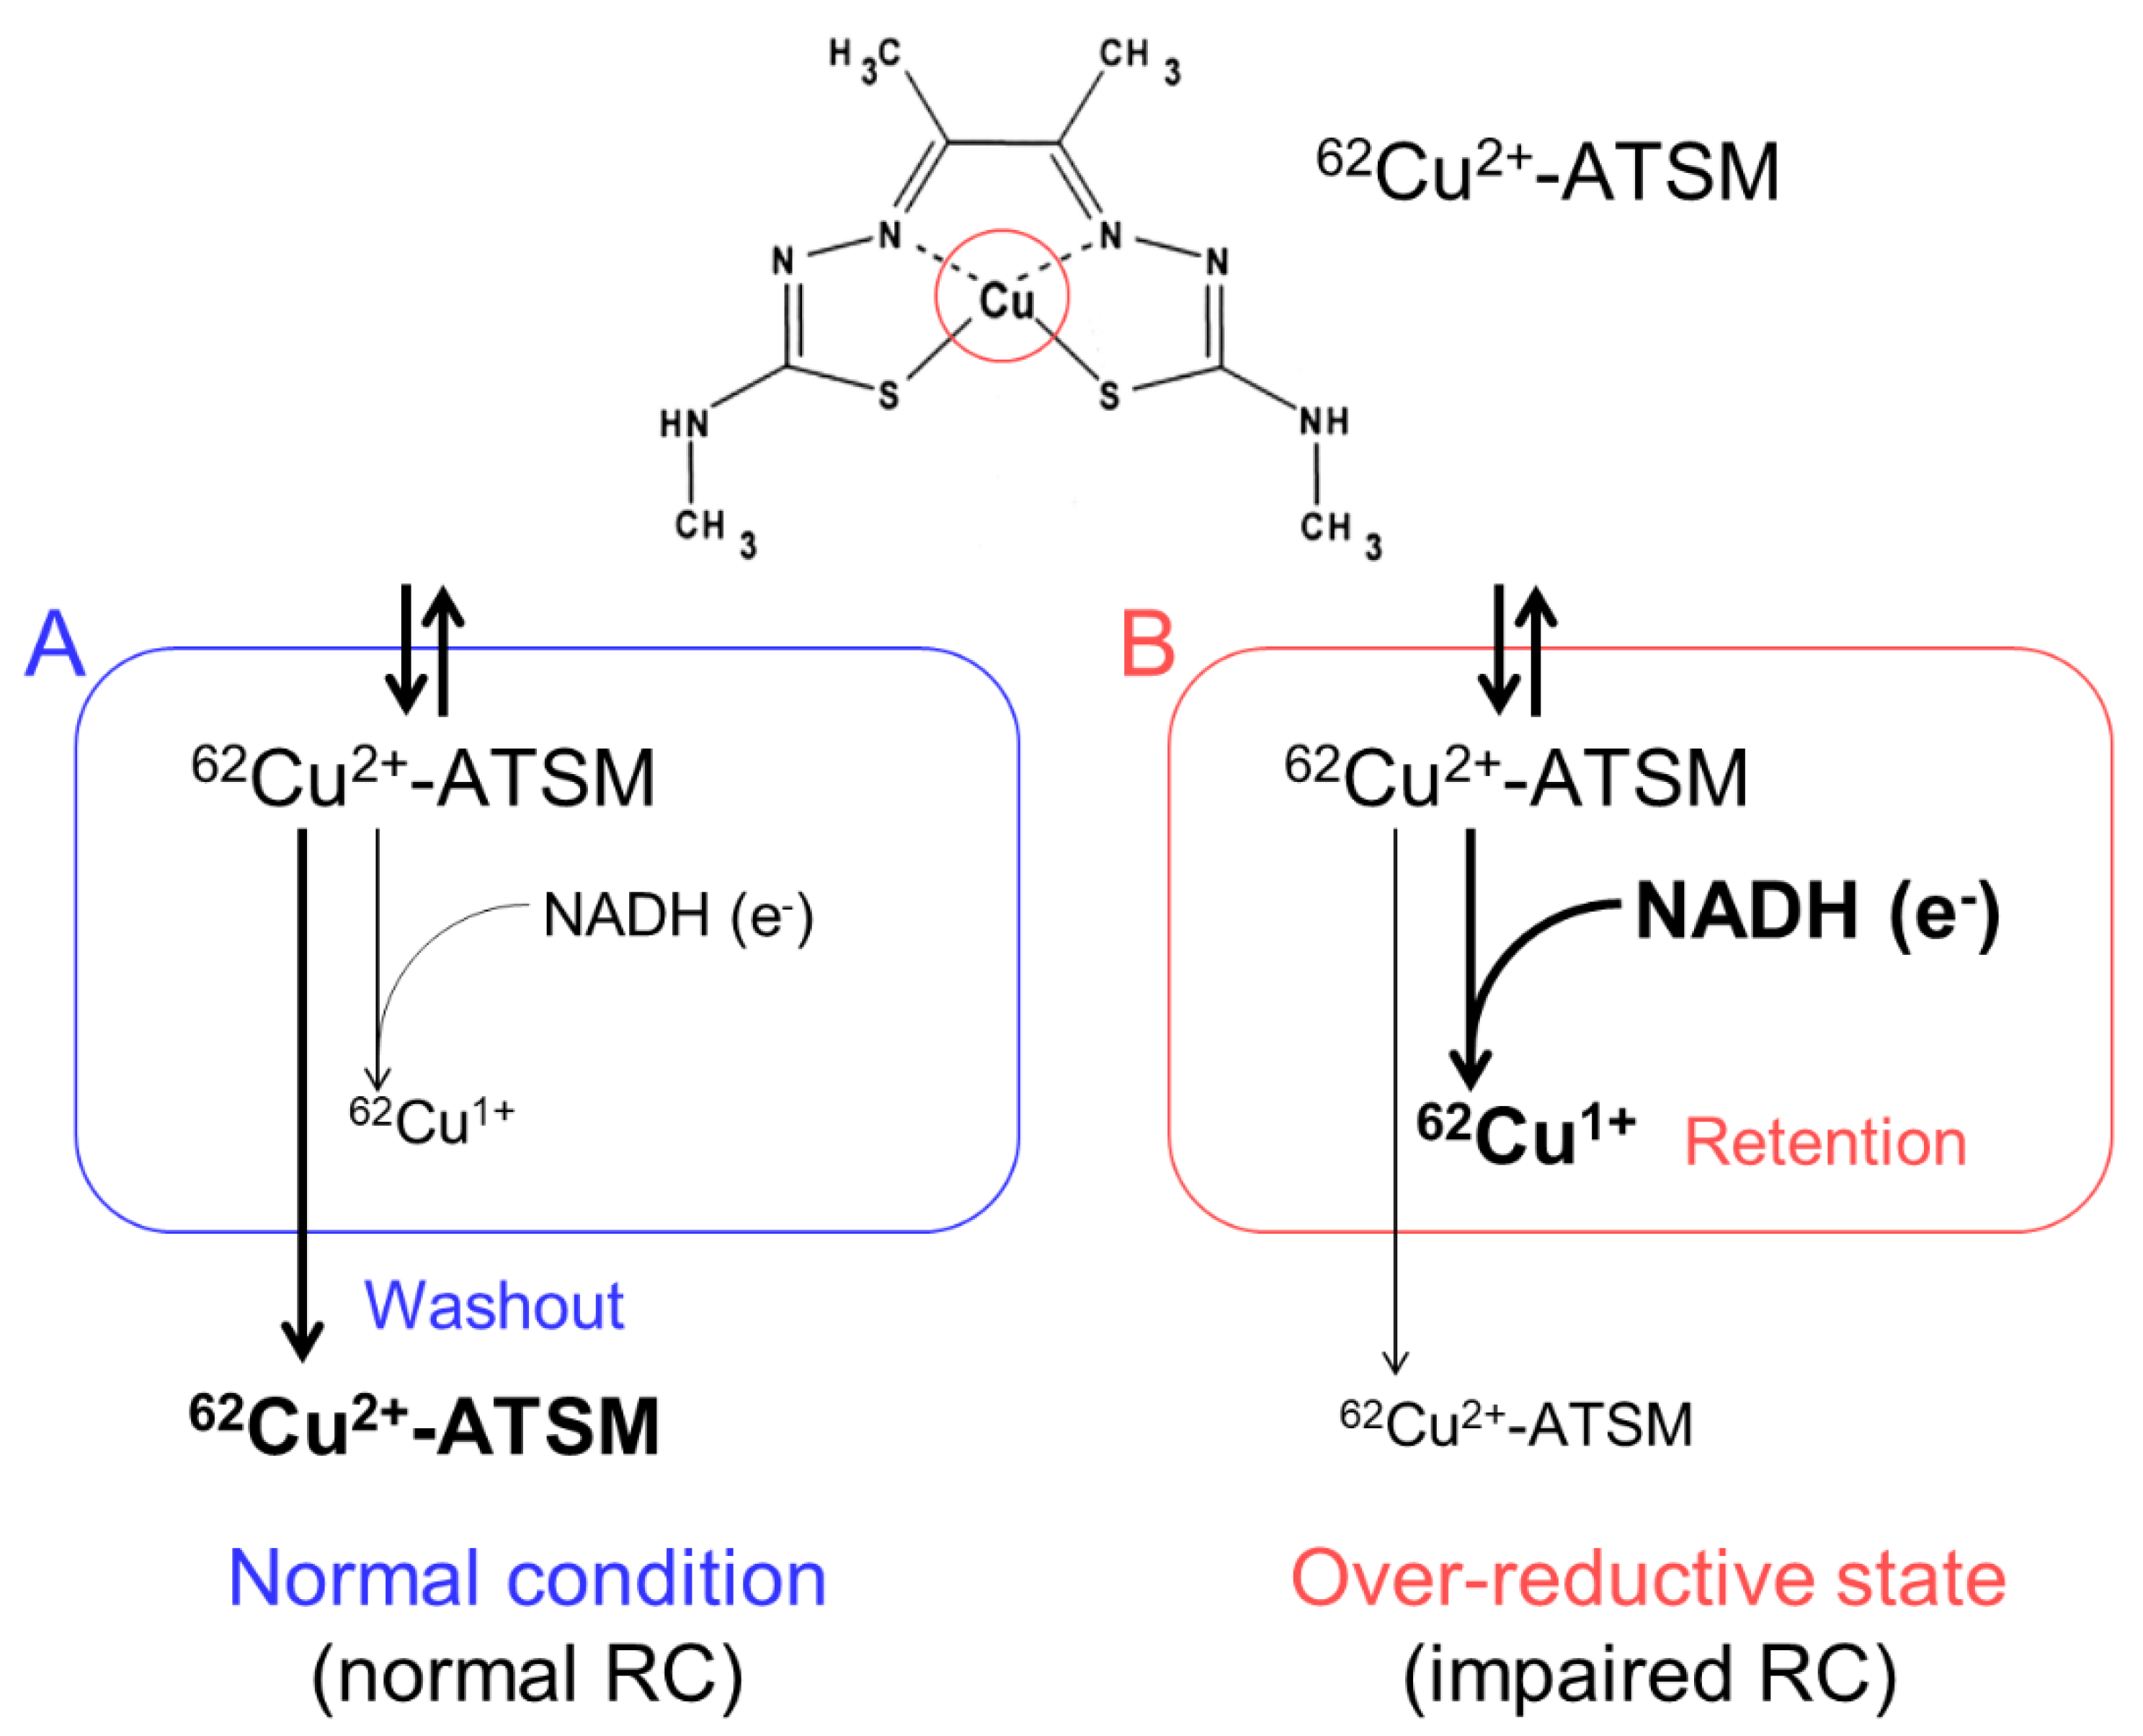

3.1. Accumulation Mechanism of 62Cu-ATSM

5.1. Oxidative Stress and Mitochondrial Dysfunction in Parkinson’s Disease

5.2. PET Imaging for Oxidative Stress in Patients with Parkinson’s Disease